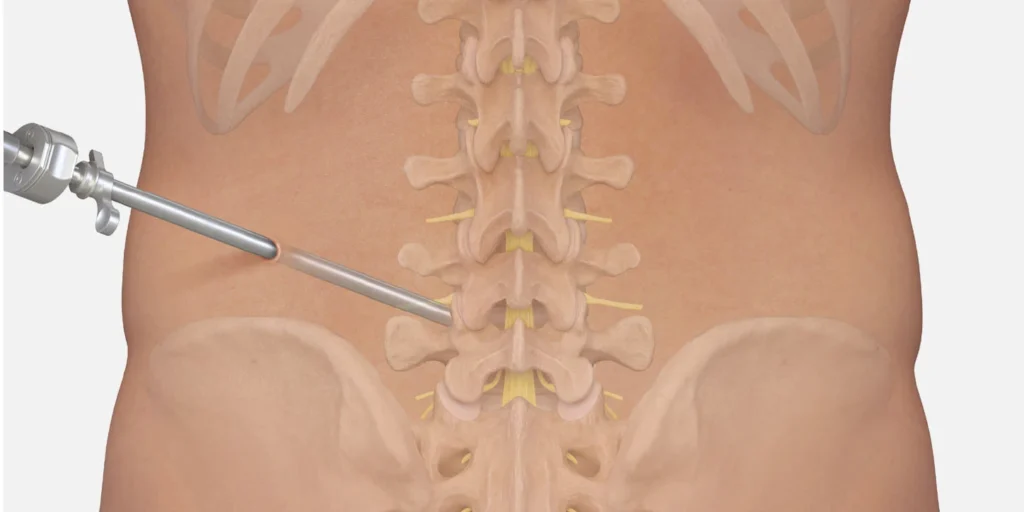

Cirurgia Endoscópica de Hérnia de Disco: Passo a Passo e Recuperação

Entenda como funciona a cirurgia endoscópica de hérnia de disco, indicações, vantagens e o que esperar na recuperação com foco em tratamento minimamente invasivo.